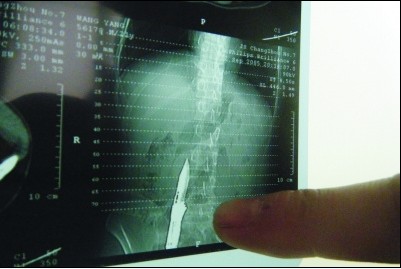

“19日清晨5時(shí)許,他(王某)被送進(jìn)醫(yī)院時(shí),刀還插在肚子上。”該院普外科醫(yī)生唐會(huì)峰介紹說(shuō),王某剛送來(lái)時(shí),一把十幾厘米長(zhǎng)的匕首只有刀柄露在外面,傷口在肚臍右側(cè),七八厘米長(zhǎng)的刀刃全在身體里,衣服上還有不少血跡。見(jiàn)此情景后,院方迅速組織醫(yī)護(hù)人員搶救,經(jīng)過(guò)CT判斷,刀刃捅傷了大網(wǎng)膜,更危險(xiǎn)的是,刀刃距離腹下臟靜脈僅僅幾毫米,如果刀刃稍微再近一點(diǎn)的話就“沒(méi)得救了”,肯定會(huì)殃及其性命。打開(kāi)腹腔以后,里面積了300多毫升的血,經(jīng)過(guò)一個(gè)多小時(shí)的搶救,王某的傷情得到控制。王某自殘導(dǎo)致自己大網(wǎng)膜損傷和腹腔積血。目前,王某仍處于后續(xù)恢復(fù)治療中。院方已經(jīng)為王某墊付了醫(yī)療費(fèi)將近6000元,后續(xù)治療還需要2000元左右。